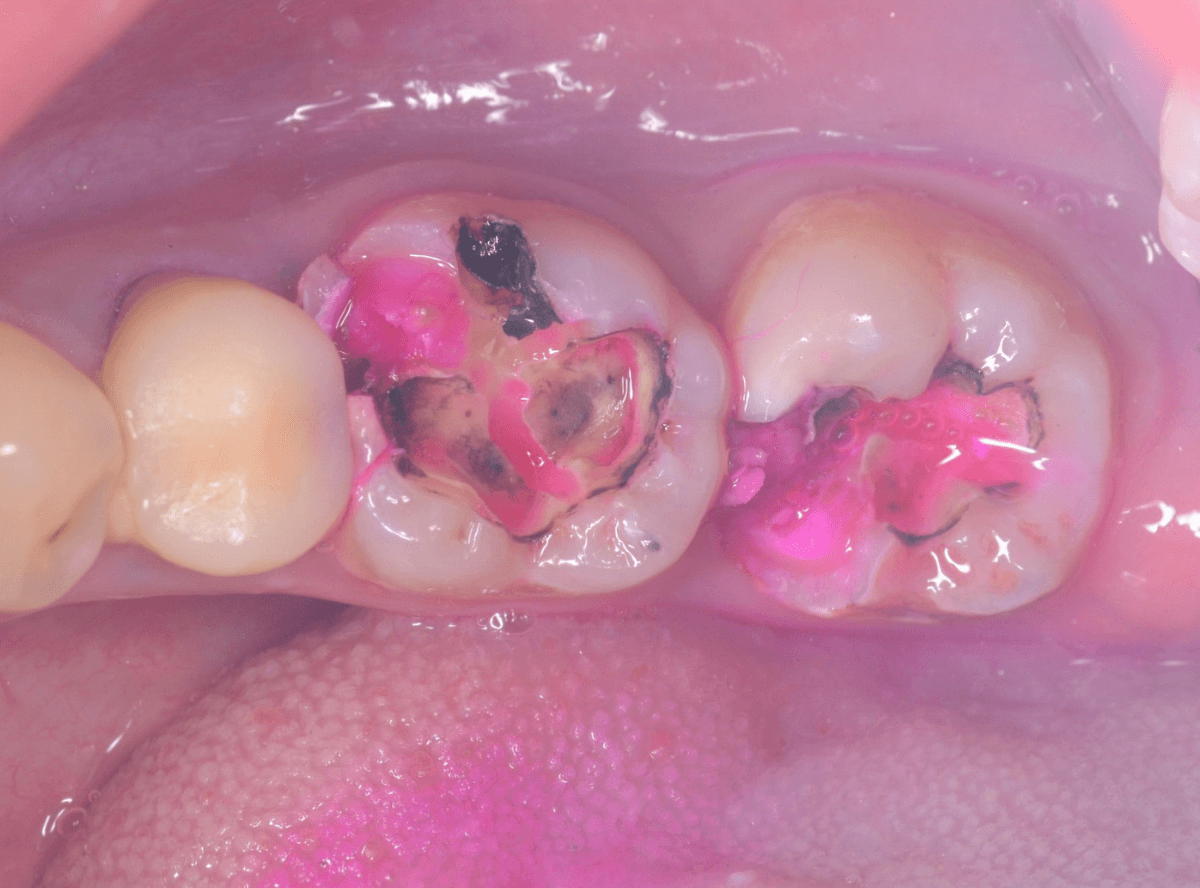

ある程度、虫歯を除去したところで、う蝕検知液で確認します。

赤い部分が虫歯です。

やはり、レントゲン写真で確認した部分が深めの虫歯になっていたようです。

〇部分は前の治療時にしいたセメントです。この下に虫歯が広がっていると思われます。

セメントを除去したところです。

赤く染め出されているところが虫歯です。

神経に近くなっていますので、診療に虫歯を除去します。

赤く染まっている部分が虫歯です。

真っ赤ですね(^^;)

まだ薄く染まっています。

もう少し除去する必要があります。

赤く染まったところが虫歯です。

真っ赤に染まっていることから、まだまだ虫歯が深そうなのが想像つきます。

虫歯を可視化する、「う蝕検知液」で染め出ししてみます。

赤く染まっている場所が虫歯で、濃く染まっているところほど、虫歯は深いです。

手前の歯は一部神経が見えそうなところまで虫歯が来ていました(●部)。